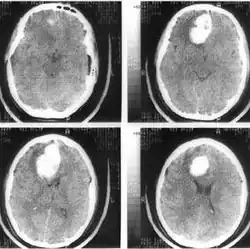

Компьютерная томография (КТ) и магнитно-резонансная томография (МРТ) — наиболее важные диагностические исследования при инсульте. КТ в большинстве случаев позволяет чётко отдифференцировать «свежее» кровоизлияние в мозг от других типов инсультов, МРТ предпочтительнее для выявления участков ишемии, оценки распространённости ишемического повреждения и пенумбры. Также с помощью этих исследований можно выявлять первичные и метастатические опухоли, абсцессы мозга и субдуральные гематомы. Если наблюдается ригидность затылочных мышц, но отсутствует отёк диска зрительного нерва, люмбальная пункция в большинстве случаев позволит быстро установить диагноз кровоизлияния в мозг, хотя при этом сохраняется незначительный риск возникновения синдрома «вклинения» мозга. В случаях, когда есть подозрения на эмболию, люмбальная пункция необходима, если предполагается применение антикоагулянтов. Люмбальная пункция имеет также важное значение для диагностики рассеянного склероза и, кроме того, может иметь диагностическое значение при нейроваскулярном сифилисе и абсцессе мозга[39]. При недоступности КТ или МРТ необходимо выполнить эхоэнцефалографию и люмбальную пункцию.